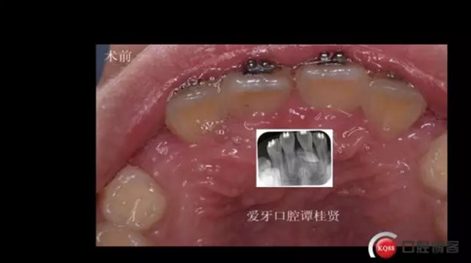

三年半前,家長領著小孩前來要求矯正牙齒,男,約八歲,兩中切牙間隙約12MM,有一多生牙,全景片顯示深處還橫著一顆,也許正處叛逆期,小孩非常的調皮,經(jīng)過幾次的各種哄和商談,也可能為了好看,終于勉強同意先拔掉露出的多生牙,前牙片斷弓關閉間隙

拔掉一顆后大概大半年時間很快就把間隙關閉了,但是由于還有一顆橫在兩中切牙間,牙縫始終得不到完全關閉,此時只能拔掉深部埋伏阻生的牙才能進一步矯正治療,但小孩一聽又要做一次手術有不同意了,這樣又拖了兩年多,長大了一些自然懂事了些。

CBCT術前分析,精準找到牙齒的具體位置